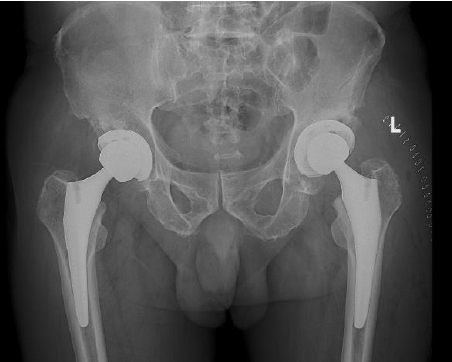

患者术后X线片(本次左髋关节置换)

患者术后影像学结果显示,假体的大小、位置、角度、肢体长度和偏心距等指标均非常理想,且与术前计划高度一致。术日当晚,患者即可下地活动,无明显疼痛,患者满意度极高。